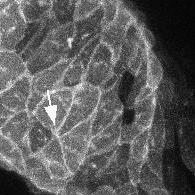

Polarisierte Zellen bringen das Herz in Form5. Juni 2018 Explantierte Zebrafisch-Herzen bilden ihre Form eigenständig in der Petrischale, (links) – nicht aber, wenn der Frizzled-7a-Faktor des PCP-Signalweges fehlt: Das Herz bleibt ein Schlauch (rechts). Bild: © Anne M. Merks, MDC Am Anfang seiner Entwicklung ist das Herz ein einfacher Schlauch. Wie sich aus ihm zunächst eine Schleife bildet und schließlich die Kammern und Vorhöfe entstehen, berichtet ein MDC-Forschungsteam in “Nature Communications”. Fast jedes hundertste Kind in Deutschland kommt mit einem Herzfehler zur Welt. Über die Ursachen solcher angeborenen Herzerkrankungen war bisher nur wenig bekannt. Mehr Licht ins Dunkel bringt nun eine Arbeit zur embryonalen Herzentwicklung, die ein internationales Team um Dr. Daniela Panáková vom Max-Delbrück-Centrum für Molekulare Medizin (MDC) in Berlin vorstellt. Durch ihre Experimente an Zebrafischen konnten Panáková und ihr Team am MDC sowie Kollegen von den Universitäten Potsdam und Zürich die Mechanismen herausfinden, über die das Herz in Form gebracht wird. Ihre Studie erscheint zusammen mit einer weiteren Arbeit zur frühen Herzentwicklung im Zebrafisch in der gleichen Ausgabe von “Nature Communications”. In dieser Veröffentlichung berichtet die Arbeitsgruppe um Prof. Christian Mosimann von der Universität Zürich unter der Beteiligung des Teams von Panáková, wie das Herz durch den kontinuierlichen Zufluss von Herzvorläuferzellen zunächst eine schlauchförmige Gestalt annimmt. Die Herzzellen müssen neue Nachbarn finden „Wir haben uns dann mit der Frage beschäftigt, wie sich aus dem linearen Schlauch zunächst eine Schleife mit ihrer charakteristischen S-Form bildet, aus der schließlich die Herzkammer und der Vorhof hervorgehen“, sagt eine der beiden Erstautorinnen der Studie, Anne Margarete Merks aus der Arbeitsgruppe von Panáková. „Für diesen Vorgang müssen sich Herzzellen der zweiten Generation dort einfinden und sich ihren Platz suchen.“ Dabei komme es zu Verschiebungen zwischen den Zellen. „Sie verändern ihre Nachbarn und finden neu zueinander“, sagt Merks. Wie sie und ihre Kollegen berichten, wird dieser Vorgang durch den PCP-Signalweg gesteuert. Die Abkürzung PCP steht für den englischen Begriff „planar cell polarity“, auf Deutsch planare Zellpolarität. Zwei Komponenten sind für diesen Signalweg offenbar besonders entscheidend: die Moleküle Fzd7a und Vangl2. „Wenn wir in den Zebrafischen die Gene für diese Moleküle ausschalteten, konnte sich das Herz der Tiere nicht richtig entwickeln“, sagt Merks: „Ganz offensichtlich fanden die Zellen ihre künftigen Nachbarn nicht mehr.“ Entscheidend ist die Spannung des Gewebes Herzzellen eines Zebrafischembryos finden neu zueinander. Nach fünf Stunden haben die fünf Herzmuskelzellen mit einem initial gemeinsamen Kontaktpunkt einen neuen Zell-Zell-Kontakt ausgebildet (Pfeil). Bild: © Marie Swinarski, MDC Der PCP-Signalweg beeinflusst jedoch nicht nur einzelne Zellen, sondern das gesamte Gewebe. „Ist der Signalweg beeinträchtigt, verändert sich die Gewebespannung“, erläutert Merks. Ohne die richtige Spannung aber findet kein Looping statt: Die Bildung der Herzschleife ist dann behindert. Wie die Forscher in weiteren Experimenten herausfanden, geht die veränderte Gewebespannung darauf zurück, dass aufgrund des defekten PCP-Signalweges das Zytoskelett der Herzmuskelzellen verändert ist. Dieses besteht aus den Proteinen Aktin und Myosin und bewirkt, dass sich Muskelzellen und damit auch ganze Muskel kontrahieren können. „Gewöhnlich beobachten wir, dass das Zytoskelett in den Herzzellen nicht überall gleich aussieht, sondern eine Polarität aufweist“, sagt Merks: „An der Oberfläche der Zellen ist es anders gestaltet als an deren Basis.“ Ist der PCP-Signalweg beeinträchtigt, geht diese Polarität verloren. Als Folge davon findet das schlauchförmige Herz nicht recht zu seiner neuen Form. „Insbesondere der Ausflusstrakt des Herzens kann sich dann nicht richtig bilden“, sagt die Forscherin. Ein Großteil der angeborenen Herzerkrankungen geht auf Störungen in diesem Teil des Organs zurück. Die Ergebnisse sind auf den Menschen übertragbar Merks und ihre Kollegen haben ihre Experimente an Zebrafischen vorgenommen, weil diese den großen Vorteil haben, dass sich ihr Herz sehr schnell entwickelt und bereits 24 Stunden nach der Befruchtung zu schlagen beginnt. „Wir gehen aber fest davon aus, dass unsere Erkenntnisse auf Säugetiere und auch auf den Menschen übertragbar sind“, sagt Panáková. „Der PCP-Signalweg ist evolutionär gut konserviert und die an ihm beteiligten Gene sind auch beim Menschen bereits identifiziert und mit angeborenen Herzerkrankungen assoziiert worden.“ Als nächstes planen Panáková und ihr Team Studien mit Herzgewebe von Erkrankten, die an den angeborenen Herzleiden Fallot-Tetralogie oder DORV (double outlet right ventricle, auf Deutsch rechter Doppelausstromventrikel) leiden. Das Gewebe erhalten sie aus einer Biobank des Kompetenznetzes Angeborene Herzfehler. Mit ihren Experimenten will das Forschungsteam nun genauer ermitteln, in welchem Ausmaß ein gestörter PCP-Signalweg an der Entstehung dieser Krankheiten beteiligt ist. https://www.mdc-berlin.de/panakova – Website der AG Panakova